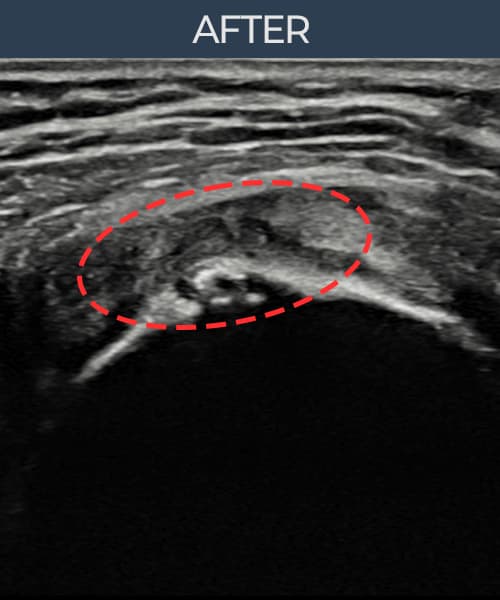

시술 전 초음파 측정 결과 파열 크기는 9mm × 5mm (힘줄 두께의 약 50% 결손)로 확인되었습니다. 시술 전 초음파에서 관절면측(articular-side) 회전근개의 부분층 파열과 힘줄 내 에코 소실 및 결손 소견이 명확히 관찰되었습니다. 시술 후 초음파에서는 관절면측 힘줄의 연속성이 회복되고 결손 부위가 재생 조직으로 채워진 것이 확인되었습니다.